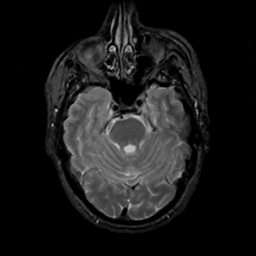

MR Study #12, May 12, 1991 -- Slice #15